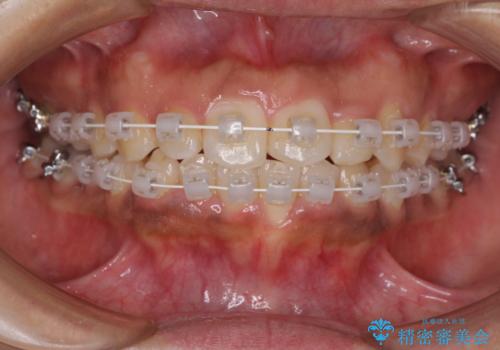

当初はインビザラインにて治療を開始しましたが、自己管理による治療が難しくなり、ワイヤー矯正へ転換して継続しました。

2年ほどインビザライン矯正を続けましたが、終了することができず、ワイヤーへ転換後は1年弱で終えることができました。